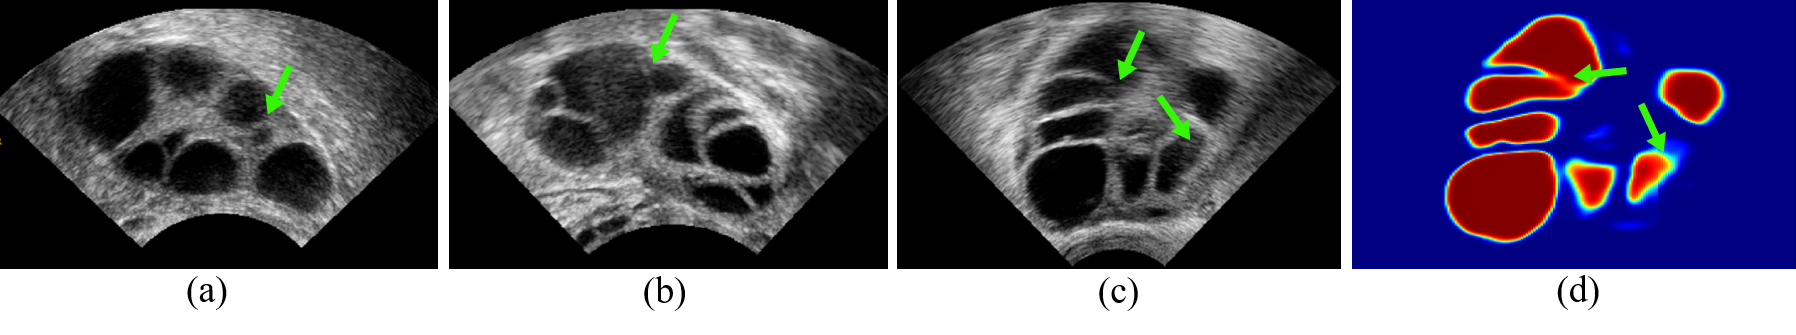

Ultrasound (US) is widely accepted in clinic for routine diagnosis. Automatically segmenting anatomical structures from US images is highly desired. US image segmentation witnessed its significant improvement in this deep learning era [6]. However, due to the low contrast, low resolution and speckle noise in US images, the accuracy of these methods is hampered in ambiguous boundary regions, such as the blurred boundary or shadow-occluded parts [5]. Taking the 3D ovarian US volume as an example, as shown in Fig. 1, the adverse effects of boundary ambiguity on segmentation are obvious. The boundary among follicles are blurring due to the speckle noise. Since the follicles have irregular shapes, varying volumes and complex connection status, boundary thickness of follicles are often inconsistent (Fig. 1(a-c)). In addition, no distinct boundary can be identified between the ovary and background tissues. All these factors can degrade the deep segmentation model with fuzzy and wrong predictions (Fig. 1(d)).

Refer to caption

Figure 1: Illustration for (a)(b)(c) ultrasound slices of ovary and follicle. Blurry boundary and scale-varying follicles are main challenges for segmentation (green arrows). (d) Follicle probability map of (c) generated by a U-net. Underestimation and touching boundary can be observed in the map (green arrow).